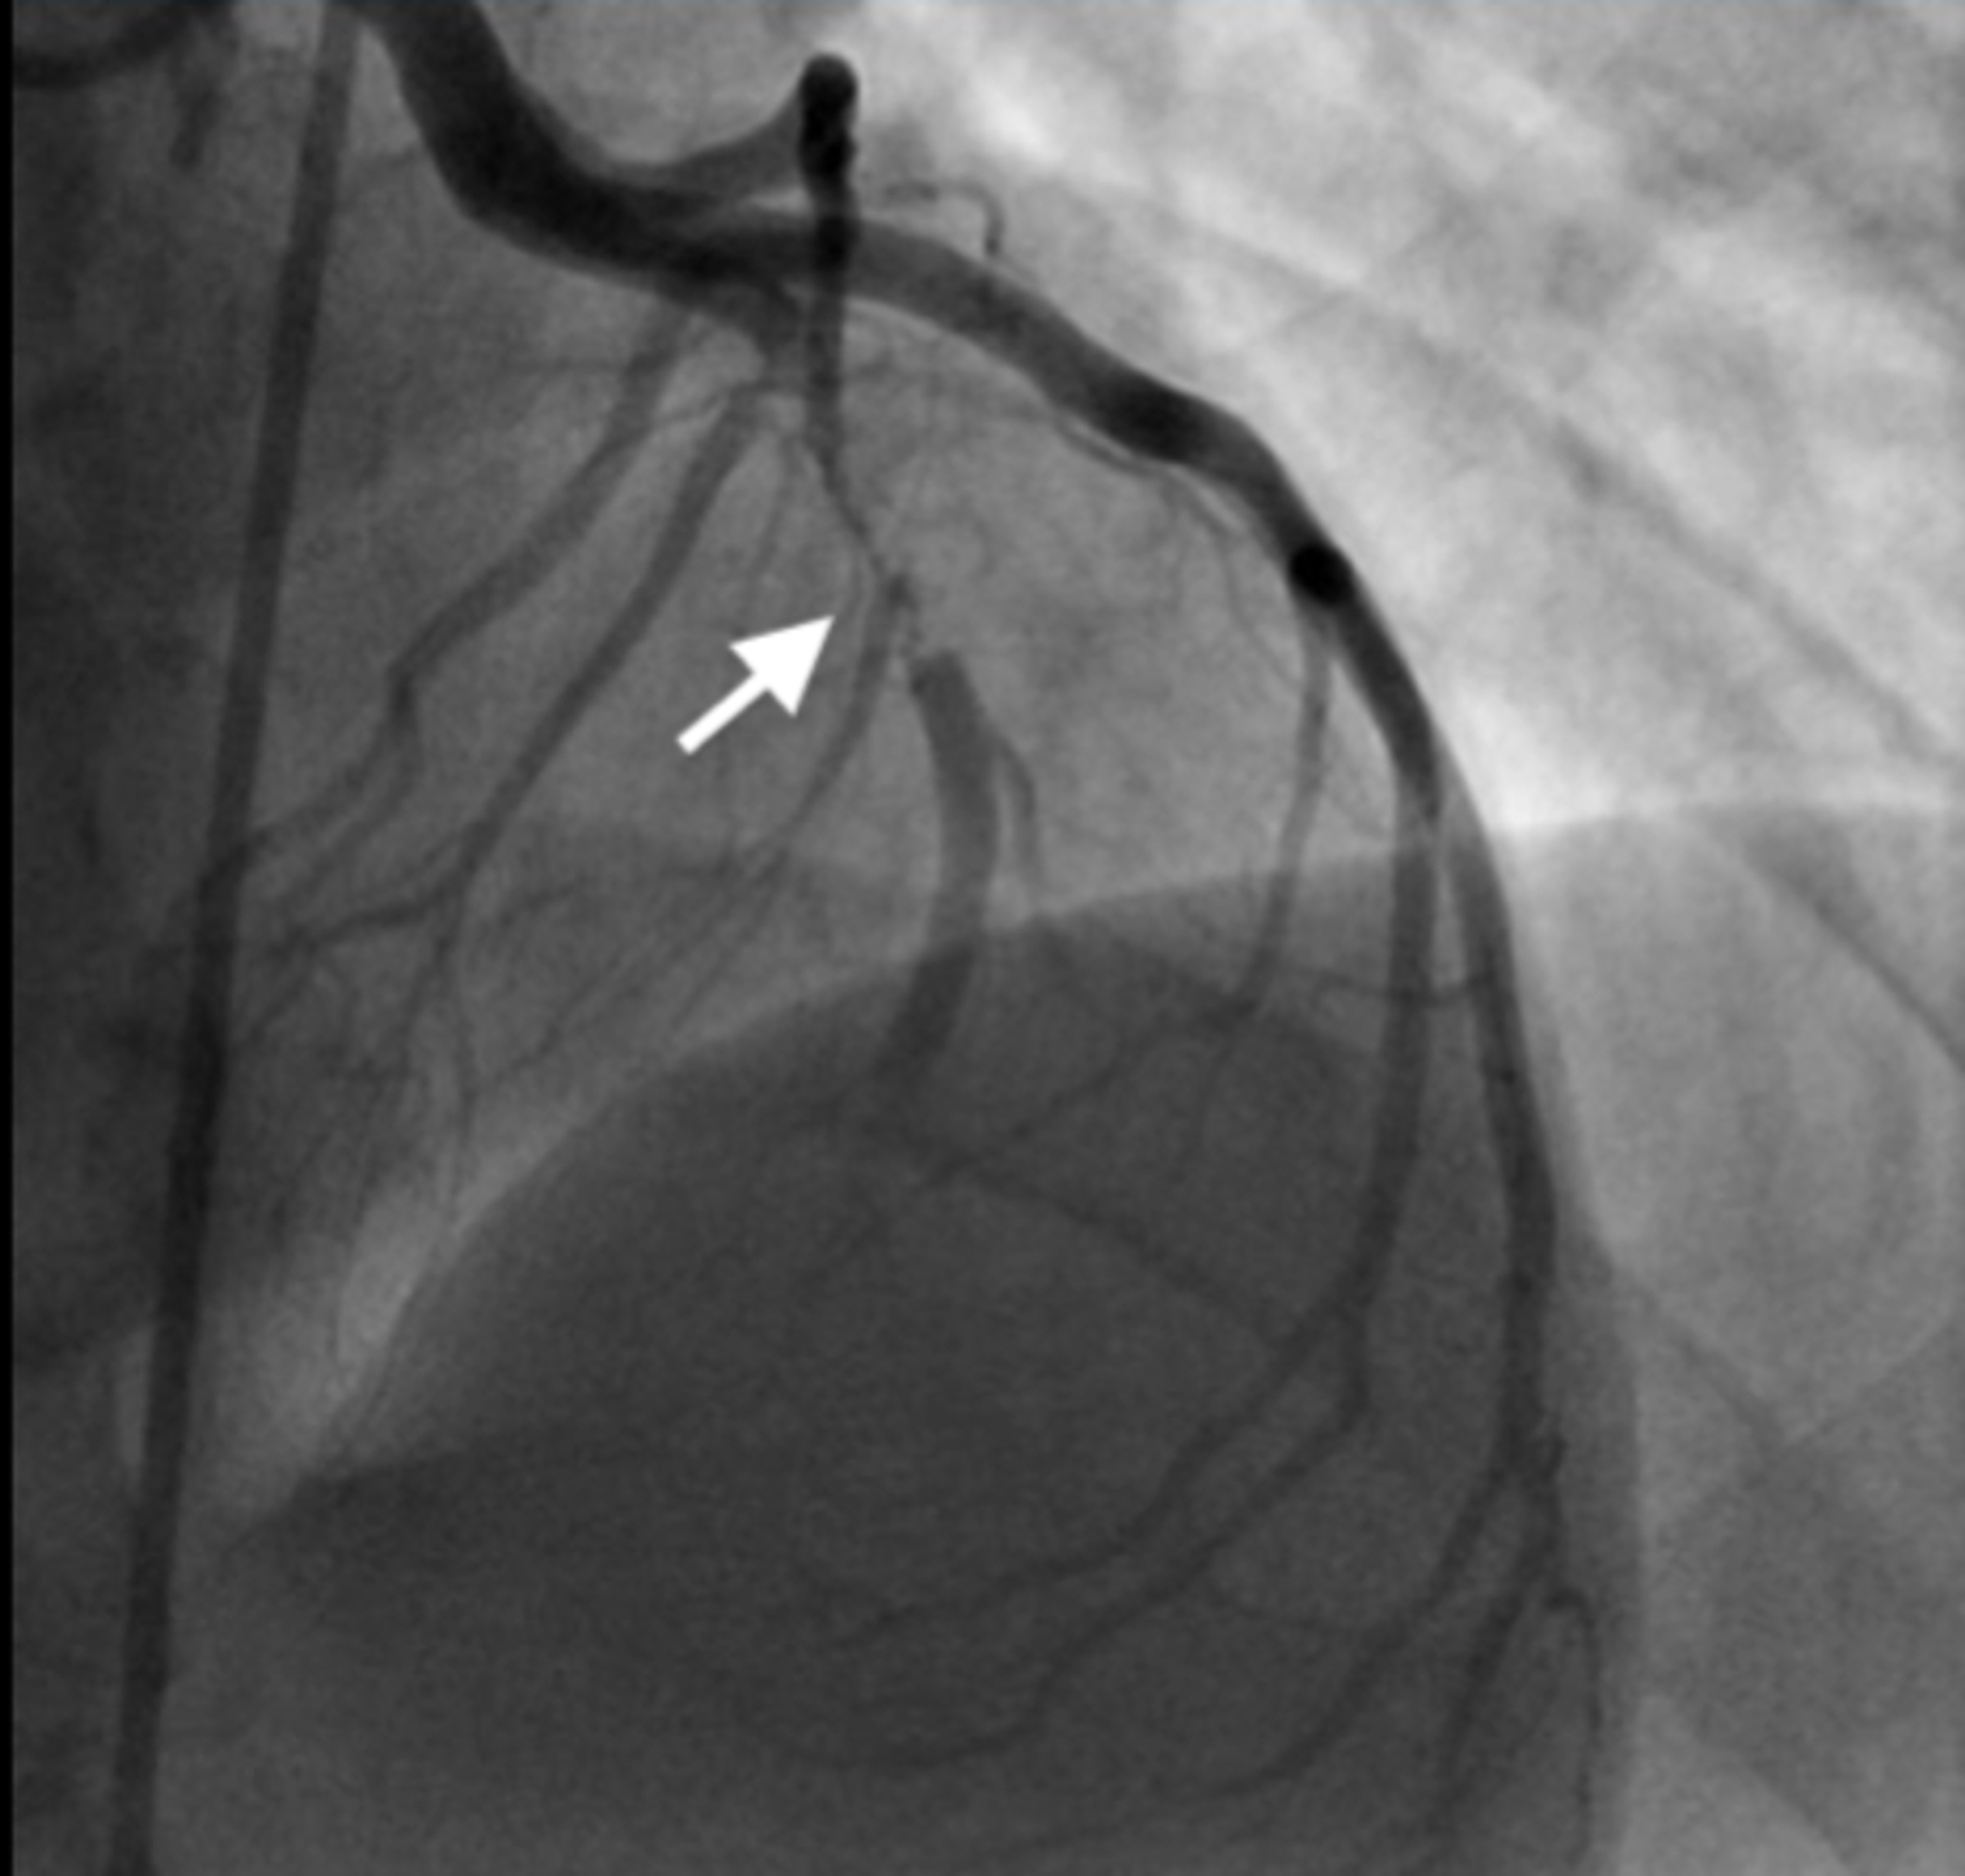

From www.researchgate.net

Left heart catheterization (left coronary angiography) Angiographically Heart Catheterization Wiki cardiac catheterization (cardiac cath or heart cath) is a procedure to examine how well your heart is working. cardiac catheterization is a procedure that provides information on how well the heart is working. right heart catheterization may be more valuable in right ventricular failure since rhc directly investigates the. cardiac catheterization, also known as cardiac cath. Heart Catheterization Wiki.